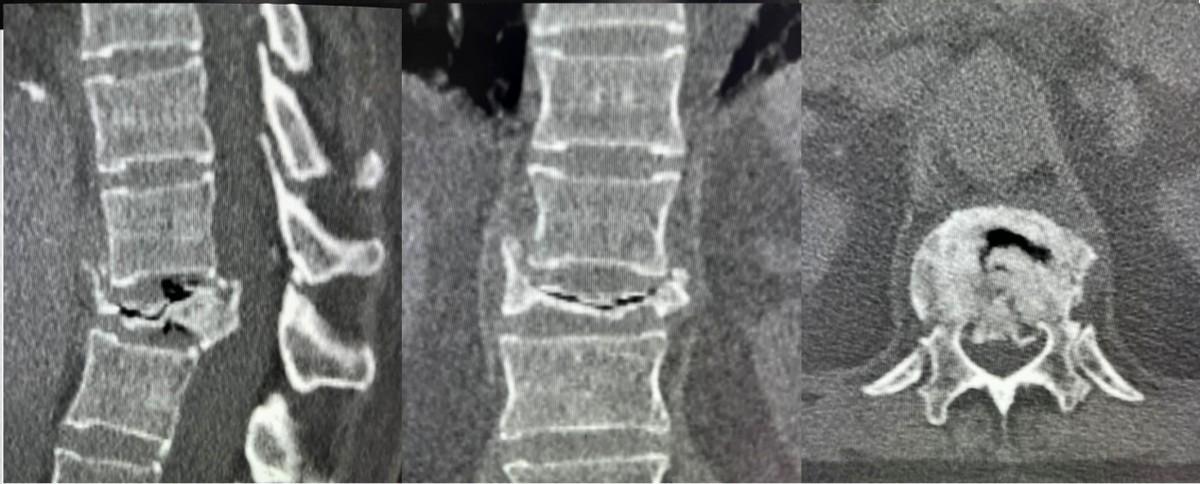

医生详细询问病史后得知,患者患有合并系统性红斑狼疮多年,并长期服用激素类药物,出现骨质疏松症,在受到轻微外伤后出现了椎体塌陷骨折。完善相关检查后,最终确诊患者为胸12椎体症状性陈旧性骨质疏松椎体骨折。

在郝定均院长及孙宏慧主任的指导下,王彪副主任医师团队采用了双枚骨水泥桥接螺钉系统完成了骨折治疗,缓解了患者疼痛及活动不便,手术圆满完成。术后,患者腰背部疼痛的症状完全消失,术后第二天便在腰背部支具保护下逐渐开始功能锻炼,恢复良好。